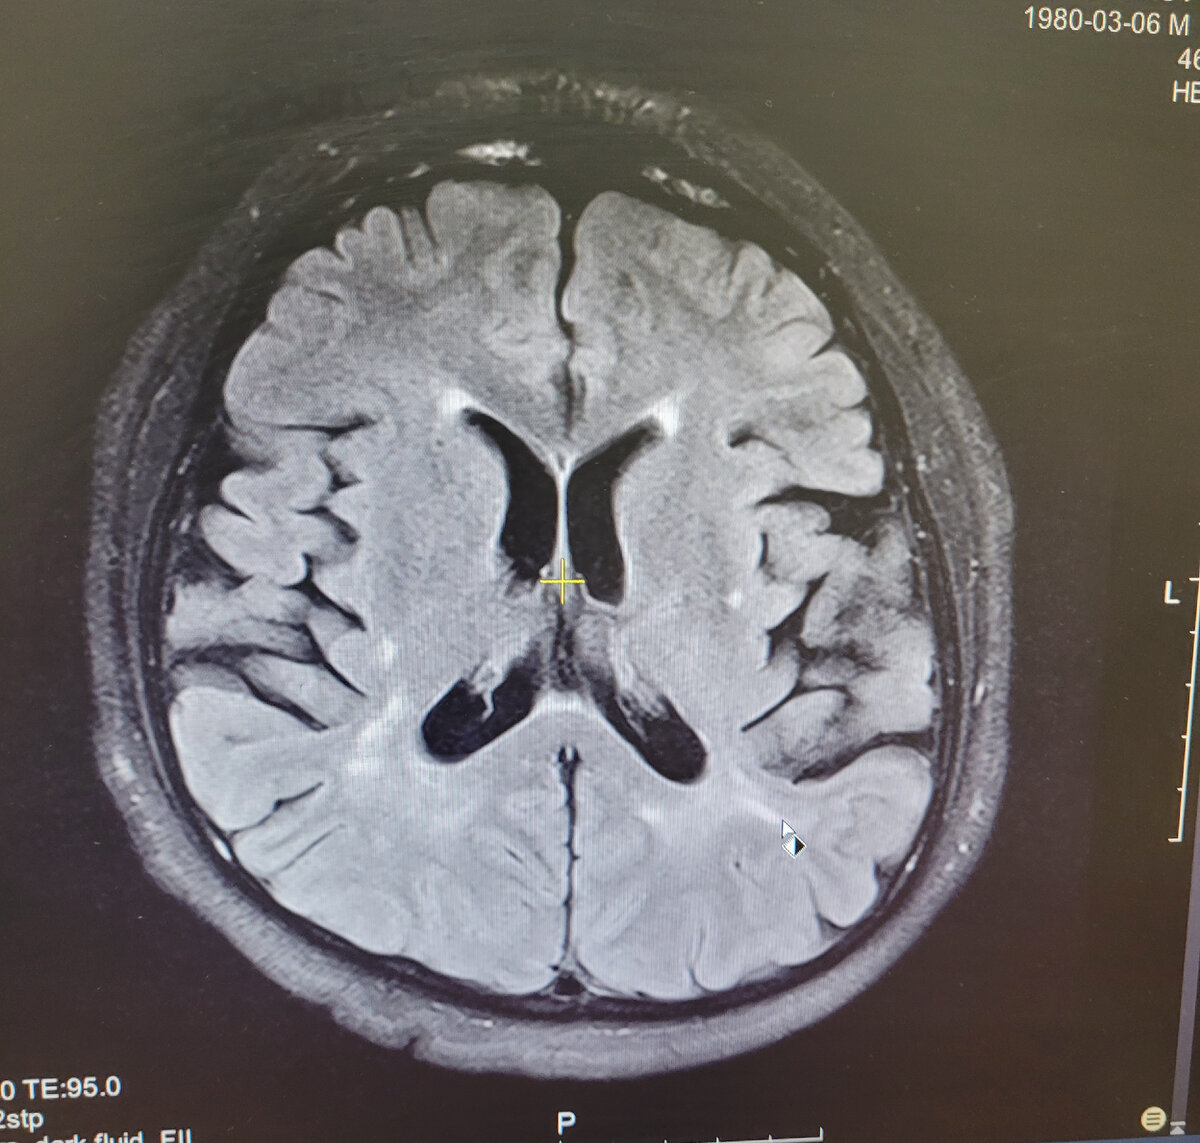

4️⃣ Сосудистая "мультиинфарктная" деменция или энцефалопатия

До 20% всех деменций, делит 2е место с ДТЛ.

Для постановки диагноза необходима чёткая связь между инсультами и когнитивными нарушениями. Только в порядке инсульт ➡️ деменция , а не в обратном.

Это именно тот, самый нежно любимый всеми врачами диагноз ДЭП - дисциркуляторная энцефалопатия, которую врачи МРТ раздают направо и налево, когда им скучно и нечего написать в заключении.

А неврологи только рады отложить голову в сторону и написать в диагнозе: ДЭП.

В реальности, если на визуализации нет очагов ишемии (хотя бы очень старой) или значимых стенозов сосудов мозга на ангиографии, интеллектуальное снижение человека на сосуды сваливать нельзя❗️